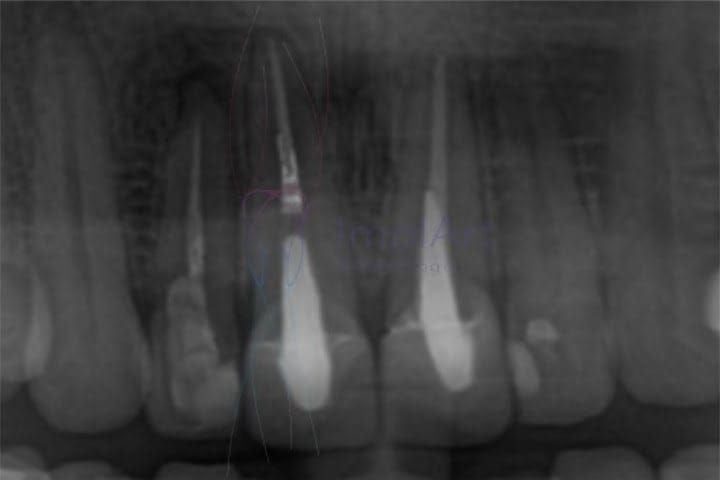

Mas nem sempre a necessidade de retratamento é uma constatado por sintomas de dor. Exames radiológicos de acompanhamento podem mostrar uma lesão ou cisto que surgiu depois do tratamento de canal, ou seja, existe uma patologia ativa.

Outra razão é quando o primeiro tratamento de canal foi realizado de forma insuficiente ou foi mal executado, seja pela dificuldade anatômica natural do dente, por falha na obturação dos canais ou falha na desinfecção.

Para isso são avaliados quais são os limite para trabalho do tratamento, ou seja, até que ponto os canais podem ser explorados sem risco de perfuração ou danos às estruturas dentais. Outro ponto a ser observado é se há desvio ou obstrução no percurso do canal.